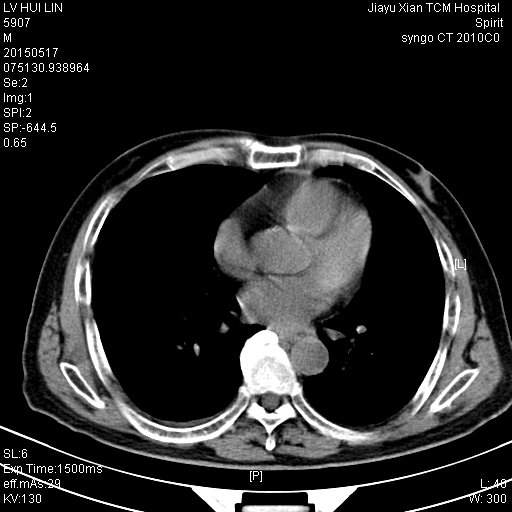

CT50460:男.73岁.腹部不适

(1)两肺多发结节灶;(2)肝内多发低密度灶;建议进一步检查

1、肝脏多发低密度灶,考虑转移瘤可能性大,建议增强扫描。

2、两肺大小不等类圆形结节,多考虑转移瘤,不除外右肺原发病灶可能。

3、胃小弯侧胃壁增厚、食道贲门密度增高,建议胃镜检查除外占位性病变。

肝脏多发低密度病灶性质待定,建议增强,胆囊小结石;右下肺占位密度均匀,边缘光滑考虑率良性肿瘤,左下肺小结节